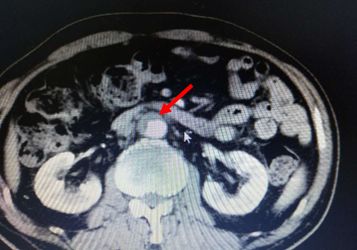

腹部CT检查结果如下:

考虑慢性胰腺炎,脾静脉血栓形成,伴脾门及胃周多发侧枝血管形成,同时合并腹主动脉夹层ⅢB型(Debakey分型),立即严格控制血压在120/80 mmHg一下,同时内科止血、输血后HGB达97 g/L转外科进一步治疗(脾切除术+胃周血管离断术以及腹主动脉支架植入术)。

本例是慢性胰腺炎所致胰源性门脉血栓引起的胰源性门脉高压症同时合并腹主动脉夹层ⅢB型(Debakey分型)。